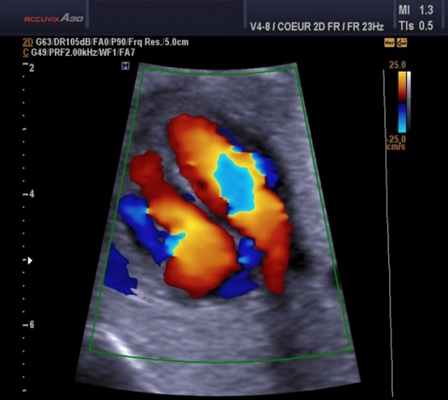

Для облегчения выявления турбулентного движения (завихрений) существует порог скорости, выше которого происходит изменение цвета (во многих аппаратах это зелены). «Мозаичный» узор на участке турбулентного потока позволяет легко установить регургитацию (смену направления движения), что помогает определить степень недостаточности клапанов.

Во время процедуры кардиолог фиксирует полученные показания. Расшифровка данных дает возможность выявить заболевания, отклонения, патологии, аномалии в работе сердца. На основе полученной информации врач ставит диагноз, назначает лечение. Зачастую дополнительно к эхокардиографии назначают допплерографию. Данная процедура позволяет увидеть направление движения, определить скорость, турбулентность потока крови в камерах сердца.